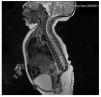

We present the case of a newborn girl from a 40-year-old mother with a medical history of untreated uterine fibroids, a background of irregular gynecology cycles, 3 pregnancies with 2 deliveries and cholecystectomy in 2008. She mentions an unplanned yet wanted pregnancy, with a high-risk pregnancy prenatal care. She attended over 15 prenatal consults. At the 18th week of gestation, compatible data with malformations of the neural tube with sacral agenesis was found, resulting in a CRS diagnosis. During the second trimester of pregnancy hyperglycemia was detected, therefore she was placed on insulin treatment. At 40 weeks of gestation, C-section was performed obtaining a healthy product, with an Apgar score of 8/9 with a gestational age of 39.6 weeks. At the physical exam we observed a weight of 3.44 kg (7.58 lbs), a length of 49 cm (19.2 in), a head circumference of 35 cm (13.77 in) and an abdominal circumference of 32 cm (12.59 in). During inspection we were able to observe an evident diabetic fetopathy, with abundant hair, and low implantation (Fig. 1). Normal anterior fontanelle (2 x 2 cm), round face, prominent cheekbones, horizontal palpebral fissures, short nasal bridge, round tip, thin lips, full palate, dysplasia of the auricular pavilions with hypertrichosis of the helix, short neck with a dorsal bulge, normal thorax, without murmurs during auscultation, the abdomen was soft without palpable masses or visceromegaly, linear spine with presence of a dimple on the skin at lumbosacral region (Fig. 2), no sacrum bone was palpable, normal position of the anus, permeable, with an absent tone. There was an evident shortening of the lower extremities and bilateral varus club foot (Fig. 3). X-rays were taken in order to see the bone malformations, and we were able to observe complete agenesis of the sacrum with a lumbar-iliac fusion. A brain and spine magnetic resonance imaging (MRI) (Fig. 4), reported an abrupt chord and lumbar termination at L3 level. After this level we are able to identify only amorphous masses with fat signal intensity, related to subcutaneous tissue. Short spinal cord, flat conus medullaris at T10 level, both iliac bones were hypoplastic, and fused at mid-level. We are not able to see the sacrum. It was possible to see both kidneys malrotated and hypoplastic, a prominent urinary bladder compatible with a neurogenic bladder. The brain image was reported as normal. An upper abdomen echography was requested in order to rule out other visceral anomalies finding a discrete discrepancy in the size of the left kidney, in addition to not finding its normal configuration, which suggested discrete hypoplasia as well as a possible malrotation. During their stay we performed multidisciplinary consultation, and cast splints were placed on both lower limbs. The patient remains in follow-up with Urology, Traumatology, Neurology and General Pediatrics, this in order to keep a close watch on all the risk factors and possible complications.

Figure 4 The lumbar spine magnetic resonance imaging (MRI) shows an abrupt chord and lumbar termination at the L3 level. Short spinal cord, flat conus medullaris at T10 level, hypoplastic iliac bones, fused at mid-level. No sacrum is seen.